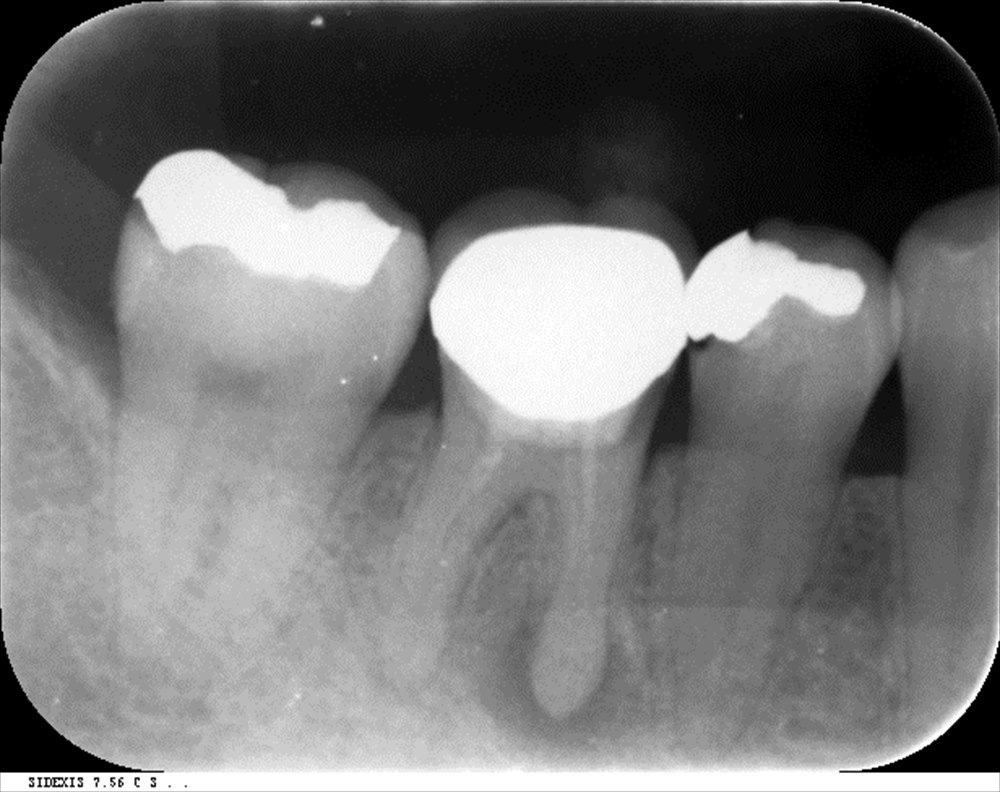

この右下6番。顔まで腫れている状態。根尖病変が大きく骨を溶かして歯茎を突き破っている状態。痛くて寝れない。。。抜いちゃえば早いですが抜きません。

石灰化も見られ難易度は高いです。湾曲もあります。

3回で根管充填

DB根はMTAで根管充填。後はガッタパーチャで。